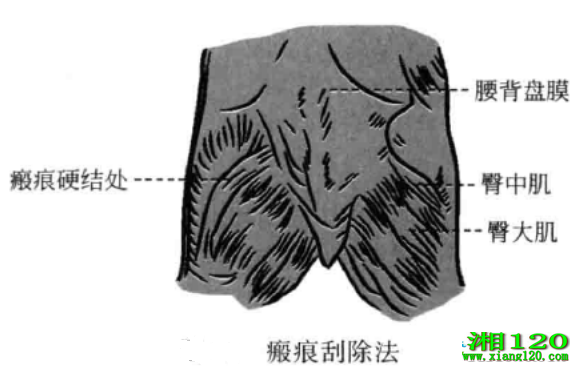

6、瘢痕刮除法

当瘢痕在脾鞘壁、肌肉的附着点处或肌腹处时,先沿着软组织的纵轴线切开数,然后在切开处反复疏剥二三次,当刀下感觉到有柔韧感时说明瘢痕已碎,即可出针。